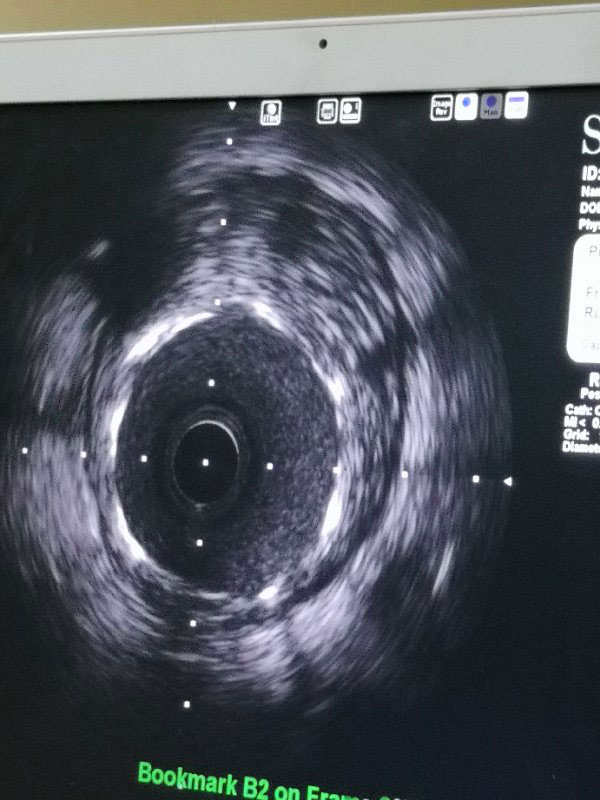

据了解,三位患者都是因严重心绞痛和非ST心梗入院,最高年龄88岁,另两名也有70多岁,是普通PCI难以治疗的危重患者。其中两名已辗转多家医院,均未得到有效救治。患者转入我院后,我院心内科在吴迪主任的带领下,经过周密的准备和科学评估,在血管内超声和临时起搏的辅助指引下,圆满完成了三台旋磨加PCI手术,术后IVUS显示治疗部位支架充分覆盖贴壁,彻底解决了三位患者的病痛,改善了长期预后。

据吴迪主任介绍,冠脉钙化病变和慢性闭塞病变一直是冠心病介入治疗的两大难题,特别是占20%比例的钙化病变,极大的难度风险及高并发症低成功率对心脏介入医生而言是巨大的壁垒和挑战。冠脉旋磨技术作为国家临床二类新技术,就是针对复杂严重钙化病变,通过特制的金刚石探头,在导丝指引氮气加压推进下送入冠脉,借助每秒高达17万转的高速旋转将钙化部位磨平断开,然后借助切割球囊分解斑块,为最终顺利植入支架创造条件。